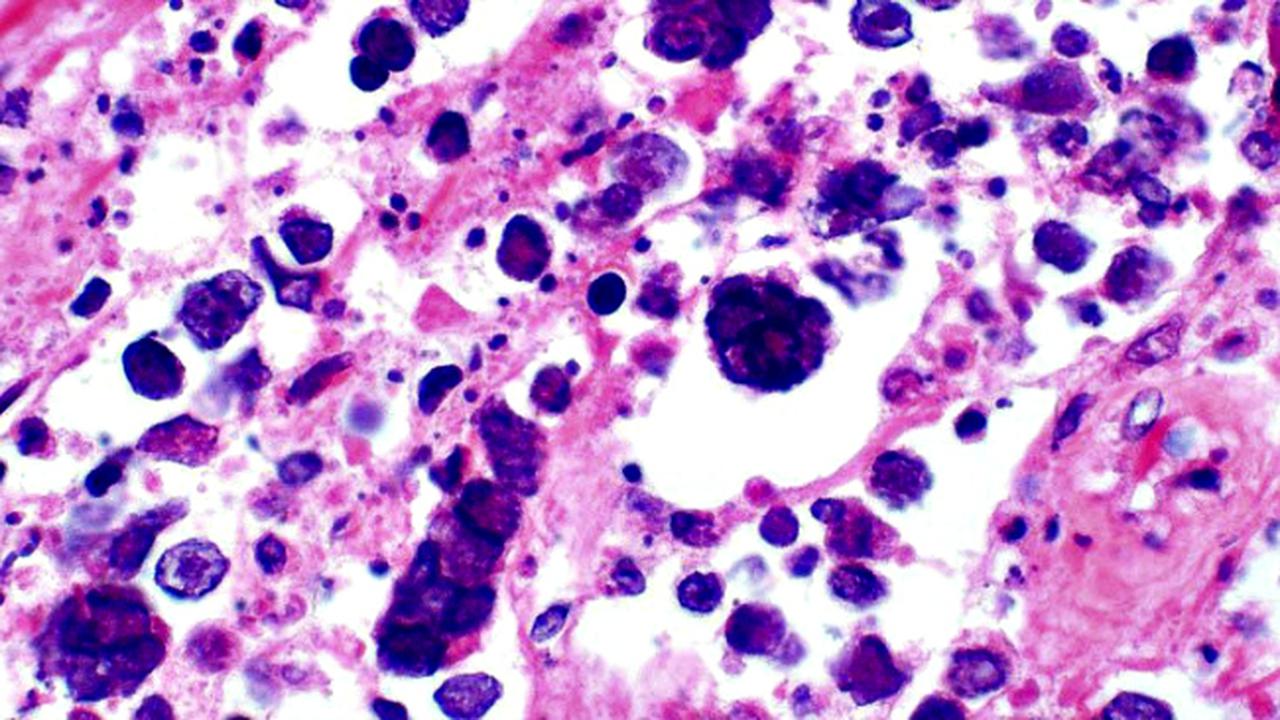

Virus yang telah mengalami modifikasi ini dirancang untuk membiak di dalam tumor dan menyebabkan kematian sel (lysis), sehingga meletuskan sel-sel itu sehingga mengeluarkan antigen yang dapat merangsang tanggapan anti-tumor. Walaupun demikian, cara yang pasti tentang perlawanan terhadap kanker oleh obat ini belum sepenuhnya dimengerti.

Dalam suatu penelitian yang melibatkan 436 peserta penderita melanoma metastatik yang tidak bisa dibedah, ada 16,3% peserta yang mendapatkan Imygic yang mengalami penyusutan ukuran bercak di kulit dan titik-titik limfa selama masa 6 bulan. Kelompok yang tidak mendapatkannya hanya 2,1% peserta saja yang mengalami penyusutan demikian.